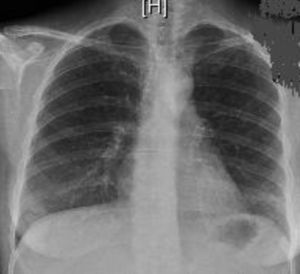

Se realiza electrocardiograma donde presentaba taquicardia sinusal a 120 lat./min con eje normal, sin otras alteraciones observadas. En la radiografía de tórax al ingreso (fig. 1) presentó varios infiltrados bilaterales bronquioalveolares de predominio en bases pulmonares y con imágenes de aspecto nodulares distribuidas por ambos campos pulmonares. La radiografía de abdomen no mostró ninguna alteración significativa.

Radiológicamente, pueden hallarse infiltrados bilaterales múltiples con nódulos que se localizan frecuentemente en los lóbulos inferiores y medios, y que miden entre 1 y 5cm de diámetro. Pueden cavitarse o tener patrones migratorios. Por lo regular, duran de 8 a 12 semanas, aunque se han informado casos más persistentes. Puede haber derrames pleurales, infiltrados alveolares difusos a consecuencia de una hemorragia alveolar, linfadenopatías hiliares y mediastínicas y daño intersticial. La TC de tórax define mejor estos hallazgos radiológicos. En el 10% de los casos puede desarrollarse una hemorragia pulmonar masiva por capilaritis alveolar, siendo esta la primera causa de hemorragia alveolar difusa, situación presente en nuestra paciente. La TC de tórax define mejor estos hallazgos radiológicos1.